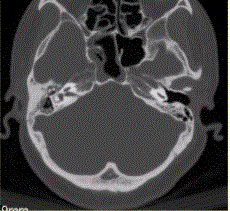

问题 患者男,20岁,外伤后右耳听力下降伴面瘫7d。临床检查,右耳传导性耳聋,发现脑脊液耳瘘。CT表现如下图。 临床拟诊为

选项 A.右侧颞骨骨折 B.右侧颞骨骨折,累及同侧外耳及面神经 C.右侧颞骨骨折,累及同侧中耳及面神经 D.右侧颞骨骨折,累及同侧内耳及面神经 E.右侧乳突骨折

答案 C